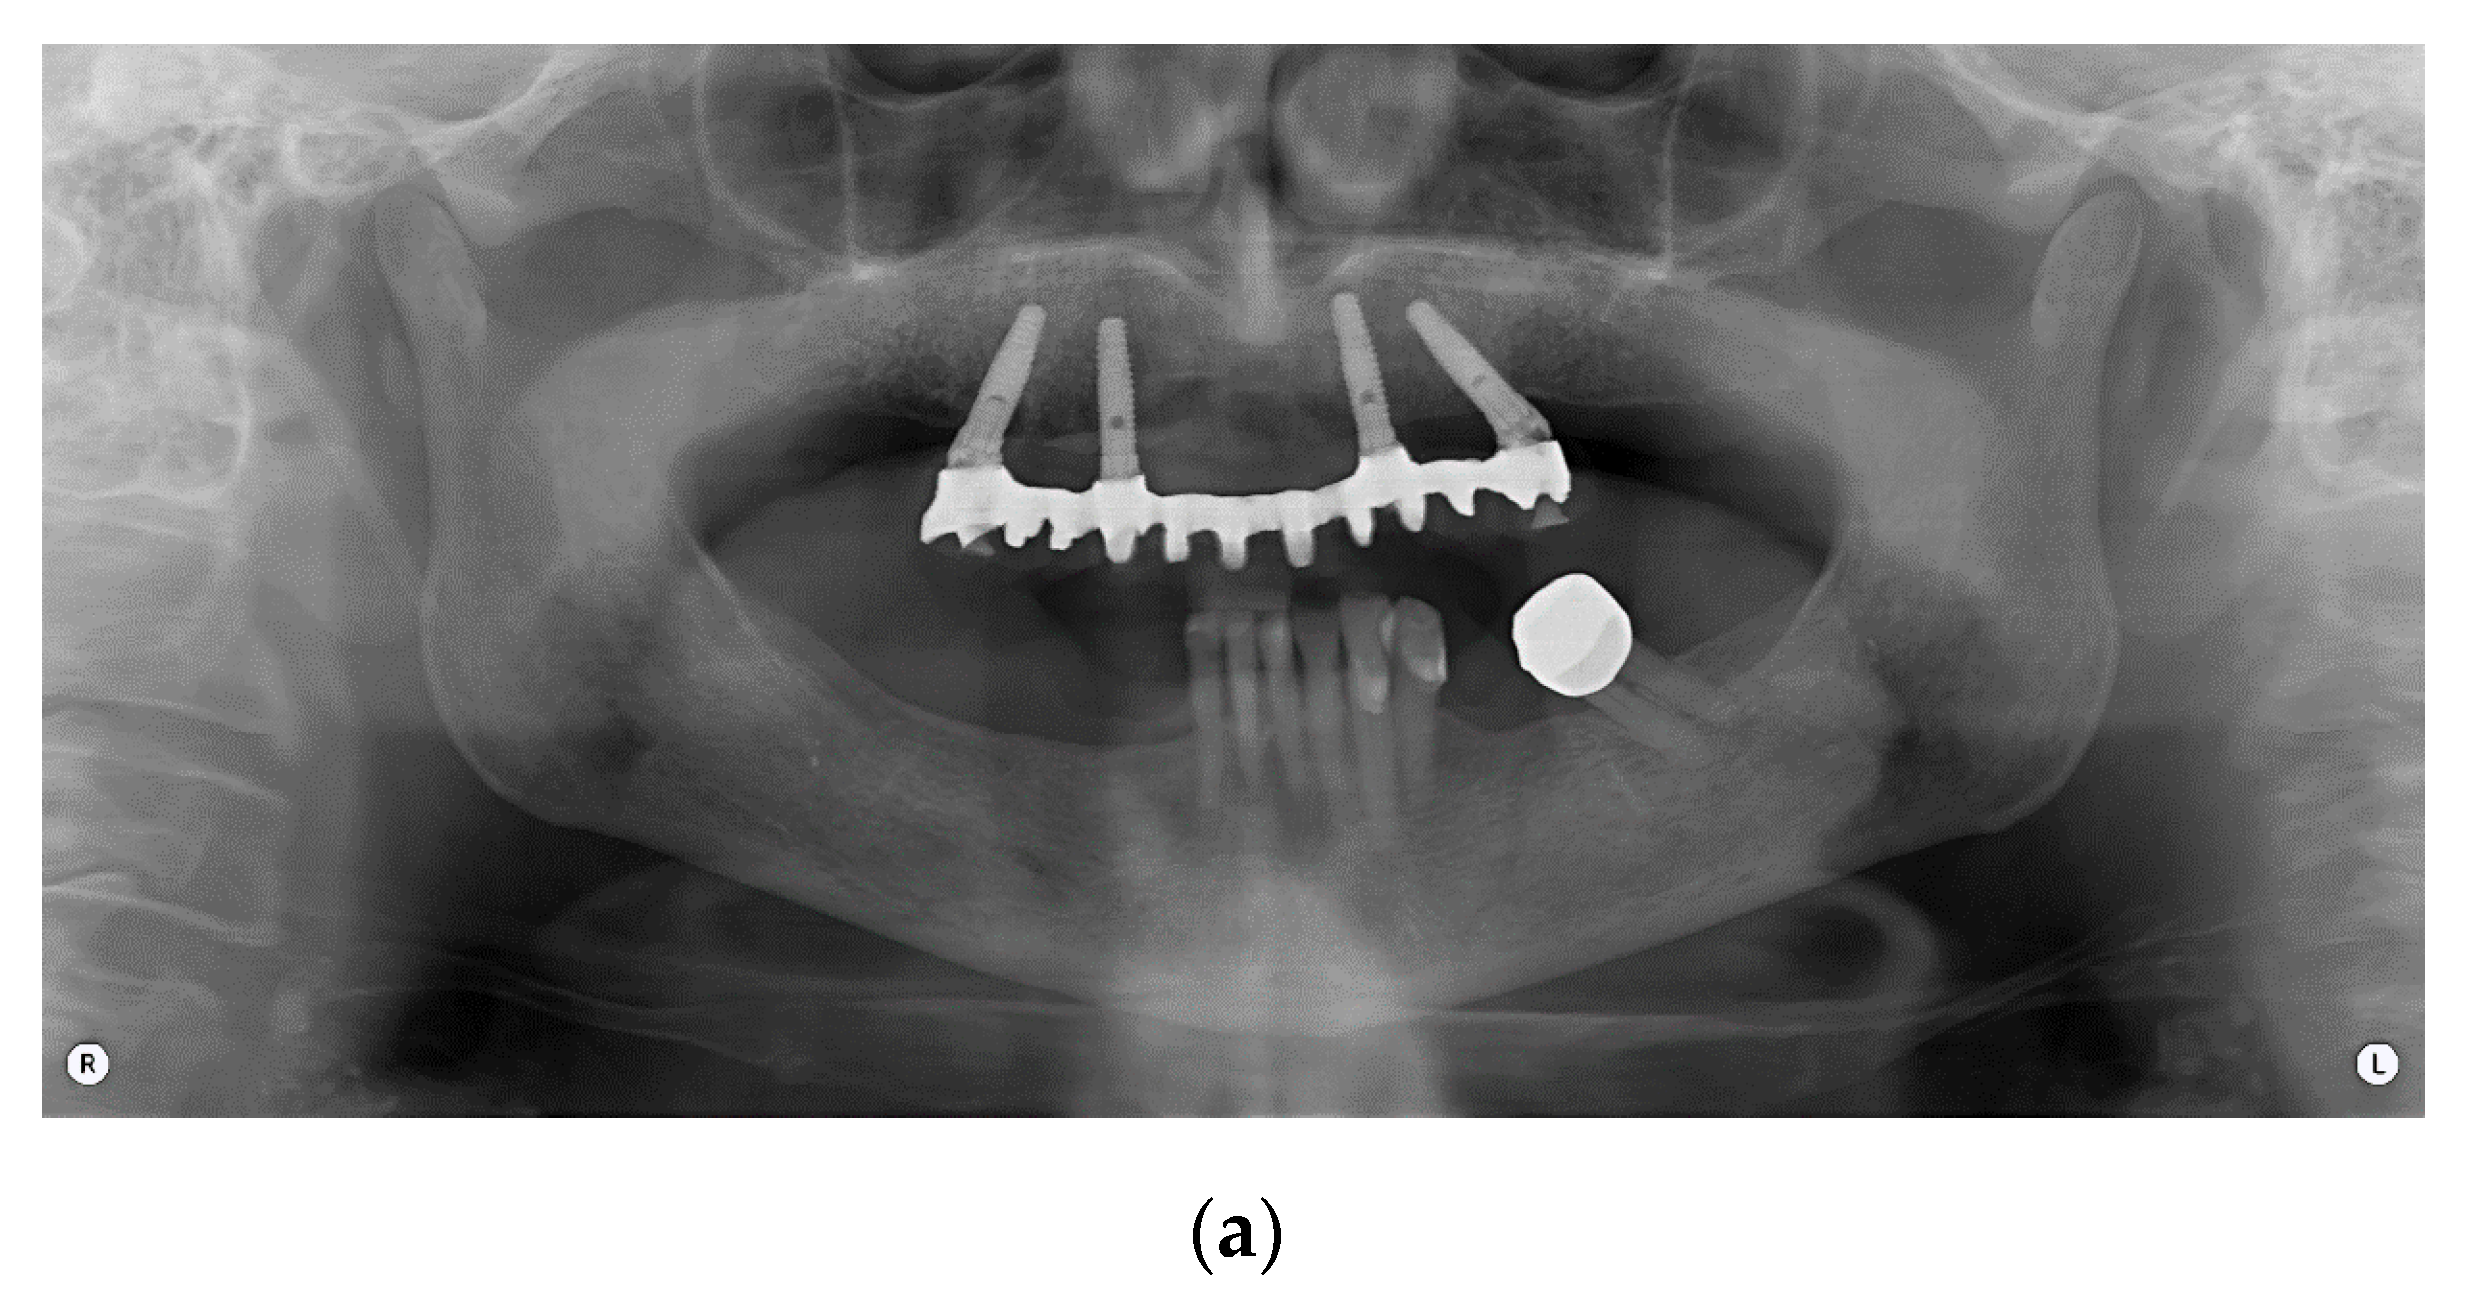

This study included 47 patients treated with an implant-supported prosthetic rehabilitation, according to the Columbus Bridge Protocol (CBP) [8,20] in the lower or upper jaw or in both dental arches (Figure 1).

The CBP protocol provides an immediately loaded full-arch, screw-retained prosthesis in the atrophic maxilla or mandible, supported by a reduced number of implants (4 to 6), with an expected delivery 24 h after surgery. Distal implants are mesiodistally tilted in order to insert long implants with high primary stability in native bone. Bone-grafting procedures are avoided. The screw-retained prosthesis is provided with a metal framework and a composite resin veneering material.

Figure 1. Panoramic radiograph of a full-arch immediate loading rehabilitation of the upper jaw according to the Columbus Bridge Protocol (a); frontal view (b) and occlusal intraoral views of the patient with (d) and without (c) prosthesis.